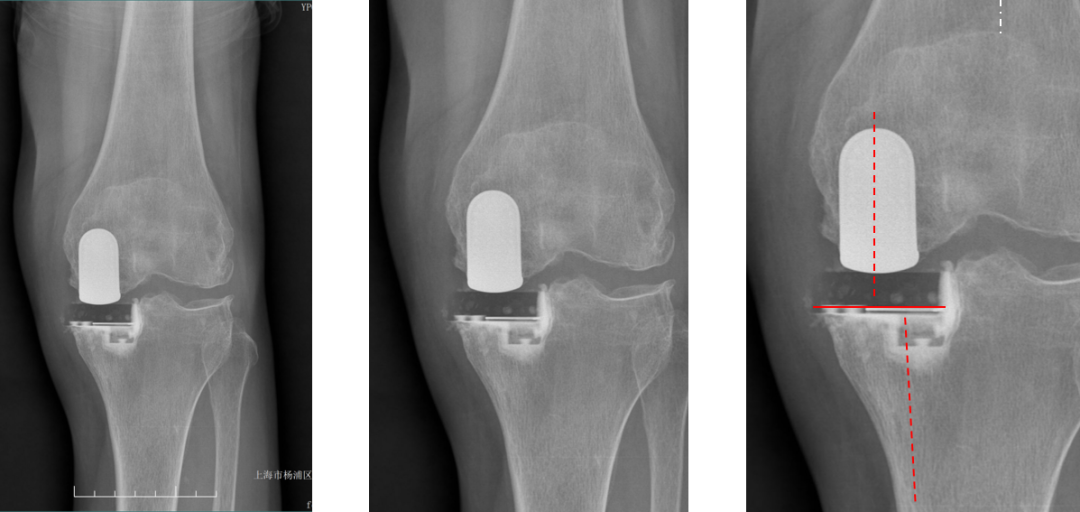

正位片标准胫骨和股骨假体位置

AP位假体位置:胫骨假体无明显内外翻,与胫骨轴线垂直,内侧缘与胫骨平台内侧缘齐平; 股骨假体长轴与胫骨假体垂直,中线一致。

胫骨假体3°内翻

AP位胫骨与股骨假体位置:胫骨假体内翻3°,股骨假体中轴线与胫骨假体垂直。

胫骨假体内侧悬挂

AP位胫骨假体位置:胫骨假体内侧悬挂>2mm。

股骨假体偏内放置

AP位胫骨与股骨假体位置:股骨假体轻度内翻,中轴线与胫骨假体中线不一致,偏内侧。